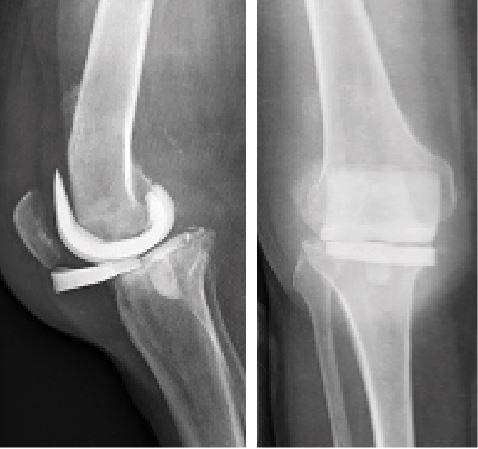

Antibiotic-impregnated cement spacers can be either static (non-articulating, block spacer) or dynamic [10]. Static spacers consist of a single block of cement inserted between the femur and the tibia (Case 1.B, 2.B, 3.B). It is non-articulating, fills the joint space and constitutes a temporary knee arthrodesis keeping the knee in full extension. This temporary immobilization leads amongst other things to joint stiffness and exposure difficulties at the time of reimplantation [9, 22, 23]. This increases the difficulty of prosthesis reimplantation and is associated with poorer clinical outcomes such as stiffness.

- Major bone loss, which is associated with a high risk of fracture, as well as a lack of fixation for a dynamic spacer (Cases 1-3).

- An incompetence of the collateral ligaments or the extensor mechanism, which can cause femoro-tibial dislocation with a dynamic spacer (Case 3).